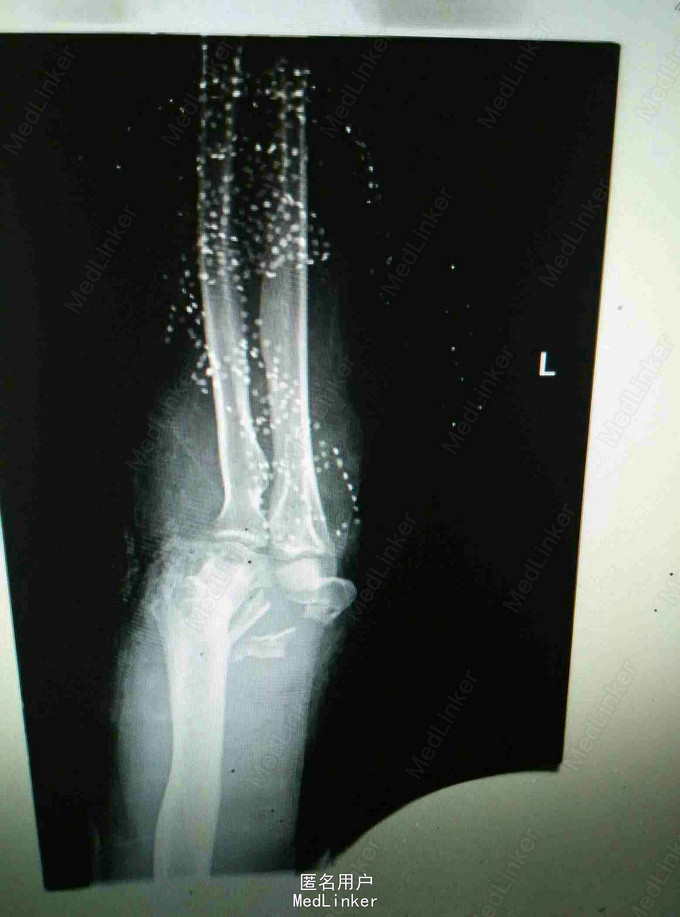

外伤致左肘关节疼痛流血,活动受限4小时 患者青年女性,因不慎摔倒致左肘疼痛流血,当即出现活动受限,肘关节可见骨外露,于当地医院行X线片提示肱骨髁间粉碎性骨折,清创包扎后入我院进一步治疗。

查体:肘关节可见骨外露,活动受限,肘后三角消失,左腕关节左拇指背伸受限,左拇指小指无法对指,五指并指困难,左手皮肤感觉减弱,以拇指小指明显 辅查:肘关节正侧位片提示肱骨髁间粉碎性骨折

诊断:左肱骨髁间粉碎性骨折 左肘关节脱位 左迟神经 桡神经 正中神经损伤 治疗:左肘关节开放伤清创术+外固定架固定术